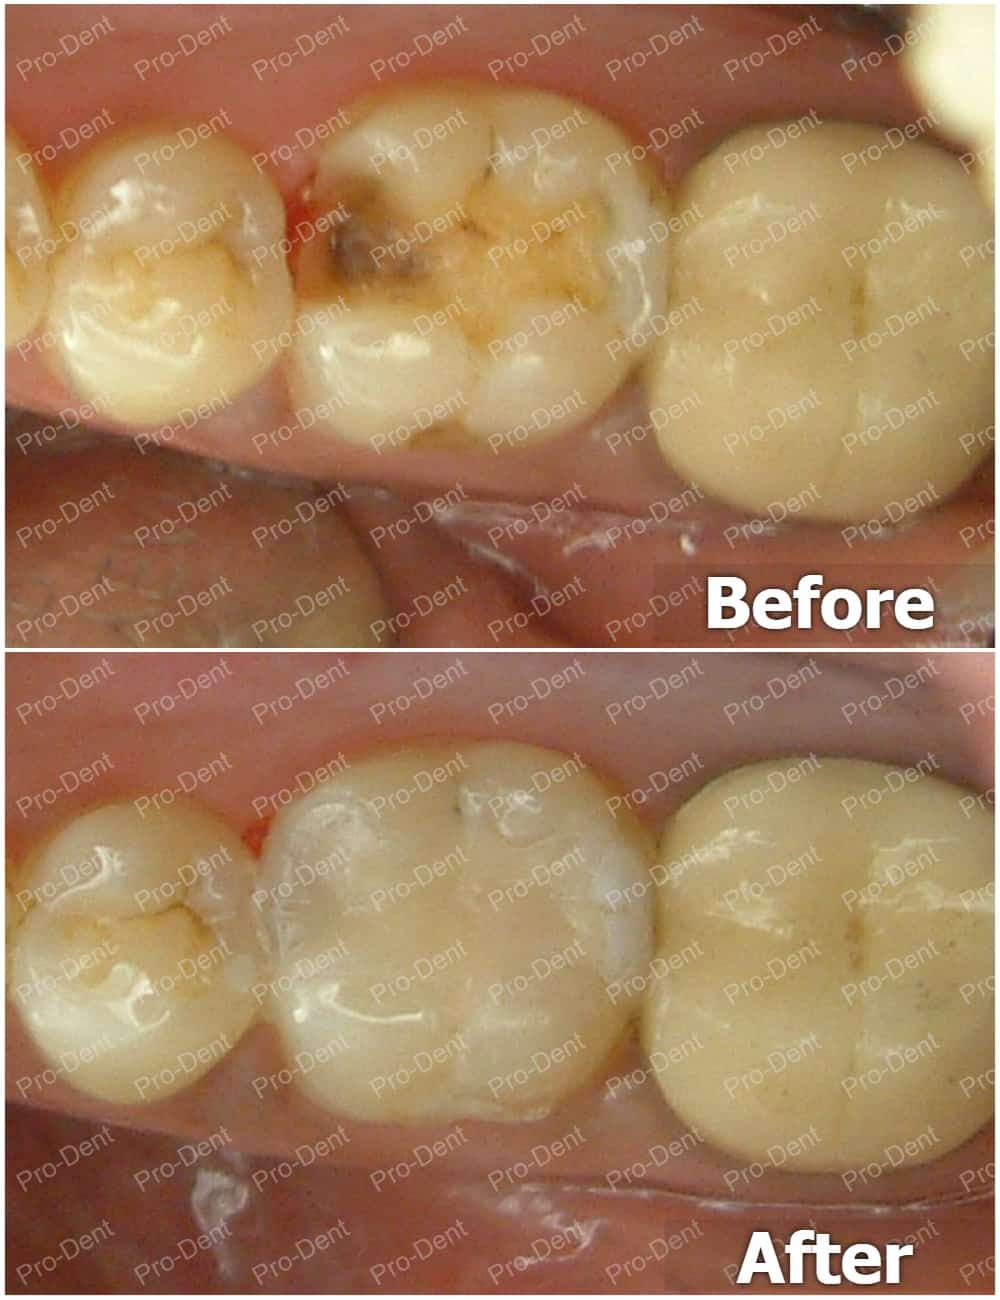

牙齒保存術-局部牙冠(3D齒雕)案例分享-實施前

牙齒保存術-局部牙冠(3D齒雕)案例分享-實施後